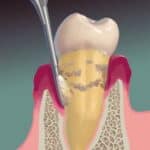

DEEP CLEANING

Periodontal Treatment that involves sub-surface cleaning and planing of the tooth to prevent tooth loss and remove pathogenic bacteria.